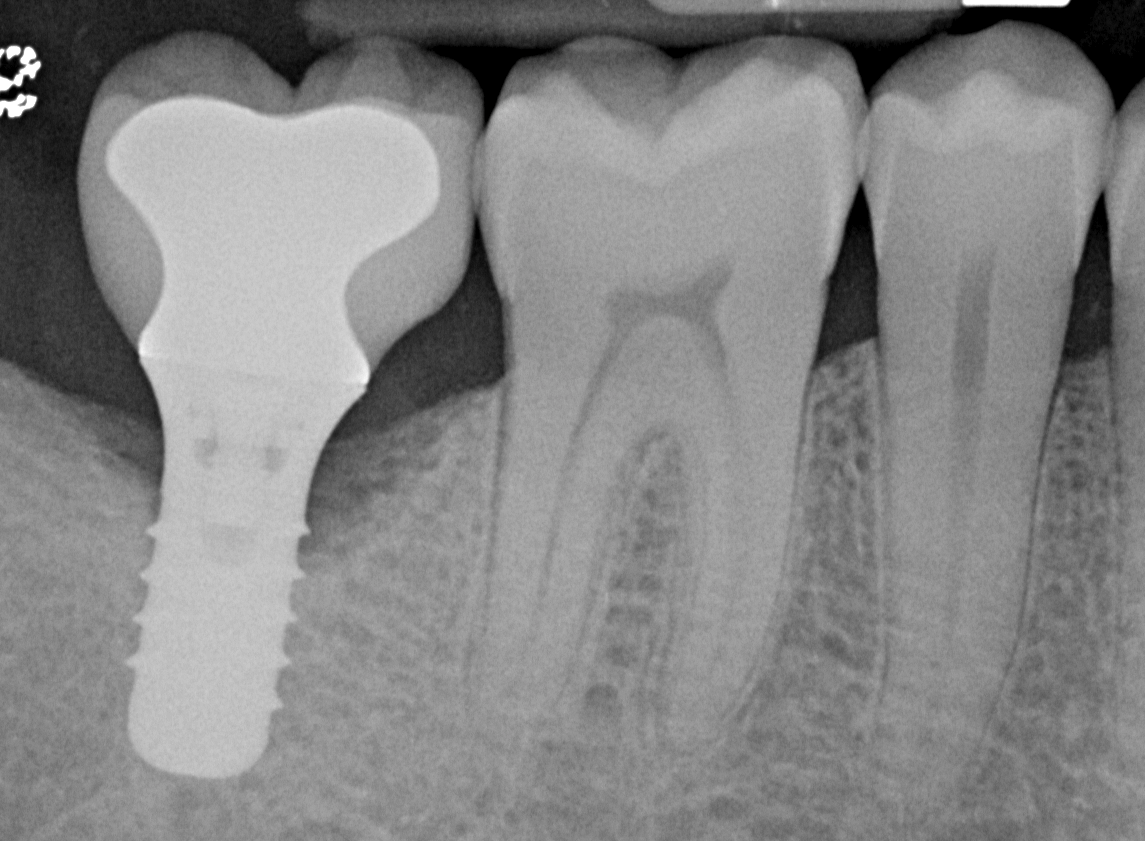

Pretreatment radiograph of a peri-implantitis

lesion on a 51-year-old male patient with a noncontributory medical history. The implant had been placed 3 years prior and presented with 8 mm pocketing with purulence.

Figure 1